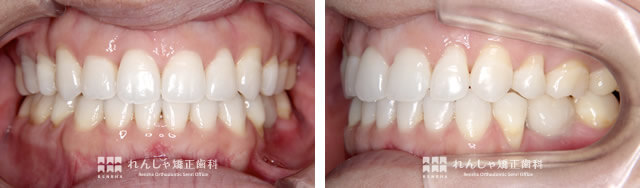

矯正治療を終えて

治療を終えた後も、C.Nさんにはリテーナーで歯並びの維持をつづけてもらっています

治療を進める上で、左下奥歯を抜歯せざるをえなくなったC.Nさん。抜歯した部分には、歯科インプラント治療を受けていただくことに。

C.Nさんは、すでに治療後8年が経過していますが、毎日ではないもののリテーナーの装着を続けてもらっています。

リテーナーの装着を面倒に思われる方もいらっしゃいますが、歯並びを長く維持するには大事な事。聞けばCNさんは、リテーナーが習慣になっていらっしゃるとのこと。実際、歯並びもしっかり維持できています。

治療前は口元のことで人の目が気になっていたと話されていたC.Nさん。矯正治療は噛み合わせの改善も当然大事ですが、心理面での好影響も期待できます。